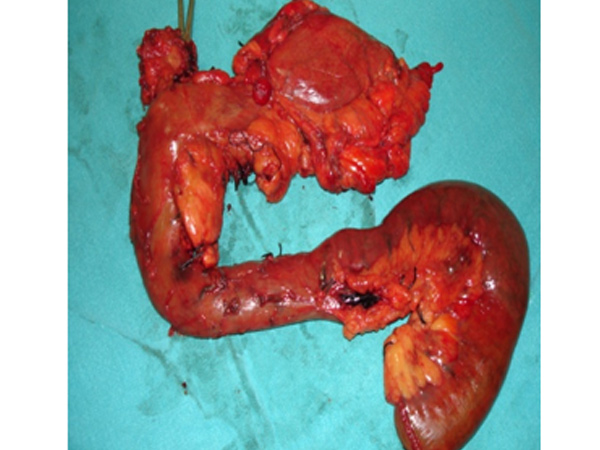

Surgery may be required for complications of acute pancreatitis like pseudocyst, bleeding or severe infection. Chronic pancreatits is associated with diabetes and malabsorption. These patients also require surgery in case of severe pain or due to any complication of pancreatitis.